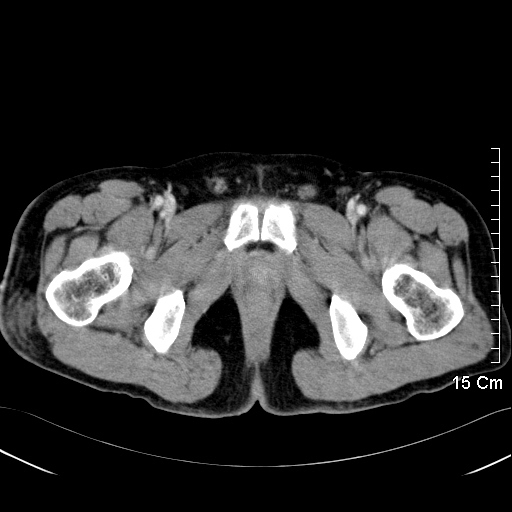

第四組影像呈現的是男生女生骨架的差異。為了懷孕生產,女生的骨盆腔會較大較圓,男生的骨盆腔顯得狹窄。古代人依屁股大小來選媳婦,便是如此道理。